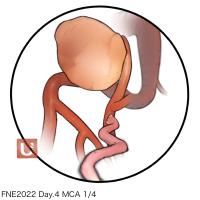

FEN2022シリーズ